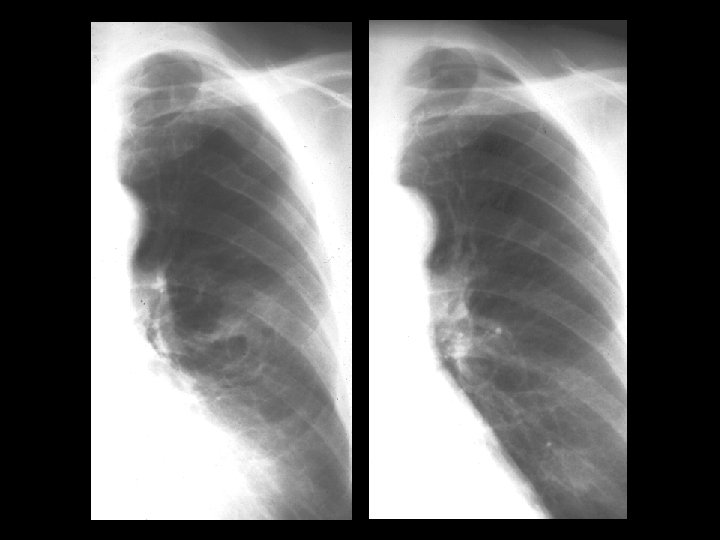

Discussion Further workup of this lesion might include biopsy to determine histology, PET imaging to assess metabolic activity, or observation over time. A valuable clue in this case is the recognition of the healed rib fracture as mentioned in the Findings section of this case. Further investigation of patient history revealed a car accident four years previously. A search for prior studies resulted in review of chest radiographs before and after the accident shown in the subsequent slide:

Discussion Review of the left image obtained two years before the initial images and following the car accident shows healed posterior rib fractures of ribs four and five and an early presentation of the lesion seen lateral to the left hilum. The right image obtained prior to the car accident shows no abnormalities. Therefore, the presumed etiology for development of round atelectasis in this case is prior trauma (rib fracture) with associated hemothorax. References • • • Hanke R, Kretzschmar R. Round Atelectasis. Semin Roentgenol 1980; 15 (2): 174 -182. Schneider HJ, Felson B, Gonzalez LL. Rounded Atelectasis. AJR 1980; 134: 225 -232. Woodring JH. Pleural Effusion is a Cause of Round Atelectasis of the Lung. J Ky Med Assoc 2000; 98 (12): 527 -532.